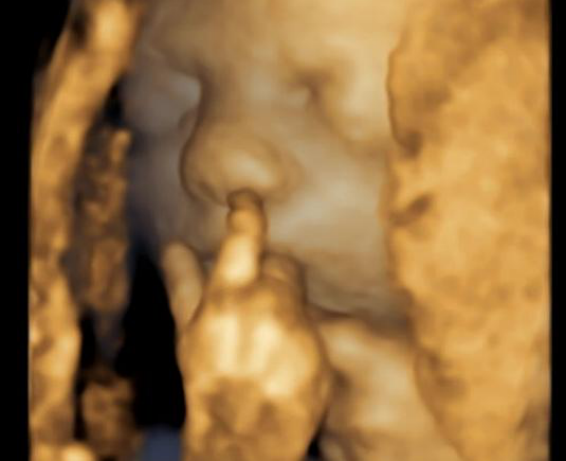

You never know what you’re going to see when the ultrasound probe starts rolling. Some babies yawn dramatically, others wave, and a few even flash the camera a peace sign (yes, it’s happened!). These moments feel like something out of a sitcom, but they’re all real, captured in high-definition detail during routine 4D ultrasound sessions.

- Pouting and Smiling: Believe it or not, babies can show facial expressions during ultrasounds. Some have even been caught“smiling” at mom and dad.